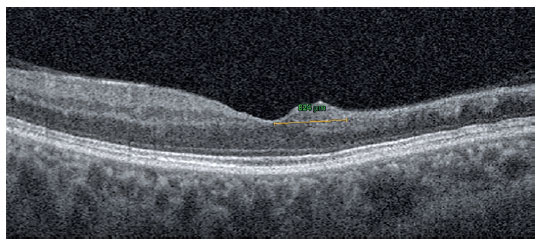

The FAZ area (mm2) in the SCP and CNP areas (mm2) was obtained via the non-flow assessment tool (Figure 3), and the FAZ area (mm2) in full retinal vasculature, FAZ perimeter (mm), acircularity index of FAZ, and foveal density (FD) (%) (foveal vessel density in a 300-µm-wide region around FAZ) were obtained via the FAZ assessment tool (Figure 4)(8). OCTA assessments were performed after resolution of RVO-ME.

06-fig04.jpg)

FD is a vessel density parameter within 300 microns around the FAZ in the FAZ assessment tool of OCTA. The device automatically detects the borders of the FAZ, draws another circle around the FAZ at a distance of 300 microns, and calculates the vessel density in this region(8). In our study, FD was significantly associated with the DRIL extent and CNP area (p=0.031 and p=0.022, respectively). The density assessment tool of OCTA also calculates the FD in both SCP and DCP. The device calculates the vessel density within a 1-mm diameter of the fovea-centered circle. However, these two parameters differ in that there was no significant correlation between the vessel density in the fovea in either of the macular capillary plexuses and DRIL extent and CNP area (p>0.05 for all). We hypothesized that this difference occurs because of the widened FAZ area in BRVO. As long as the FAZ widens, the FD will not be affected, because the device always measures the vessel density between the two circles (Figure 4). Nevertheless, in the vessel density assessment tool of OCTA, the circles are constant. The device automatically inserted three fovea-centered circles on the macula with diameters of 1, 3, and 6 mm (Figure 2). As the FAZ widens, the vessel density of the fovea in both SCP and DCP decreases. As a result, we suggest that, during the evaluation of the FD, the FD parameter in the FAZ assessment tool of OCTA should be used instead of the density assessment tool.